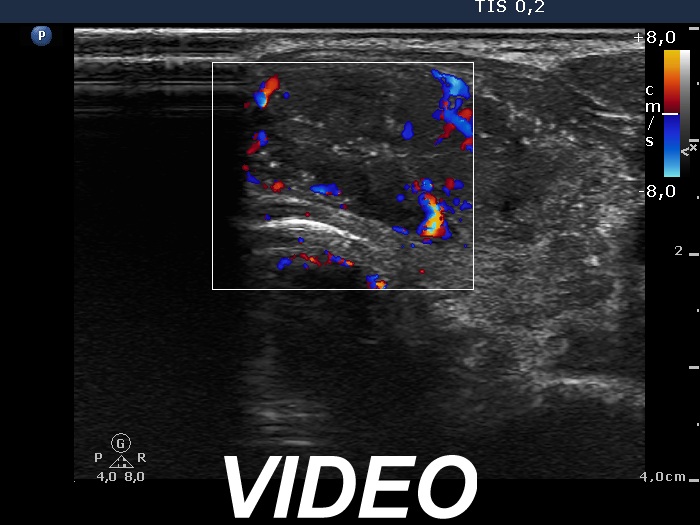

Ultrasonography revealed a hypoechogenic nodule in the ventromedial part of the left lobe. The nodule had irregular borders, contained microcalcifications and displayed perinodular and irregular intranodular blood flow.

Follow-up examination 8 years later (4th and 5th rows of images):

Ultrasonography revealed hypoechoic discrete lesions in both thyroid lobes. The lesions presented microcalcifications. Corresponding to the palpable mass in the right submandibular region, a reactive-type regular lymph node was found. There was an enlarged lymph node in the left submandibular region. The node had a regular hilum but displayed a heterogeneous pattern.

Wash-out thyroglobulin levels were 0, 81.1 and 104.9 ng/mL, right submandibular lymph node, left thyroid bed lesion and left submandibular lymph node, respectively.

Comment. Until the final histological examination is completed, I would like to draw attention to two things. One is the heterogeneity of the left lymph node and the other is the size and structure of the lesions in the thyroid beds - these features are suspicious of thyroid cancer.